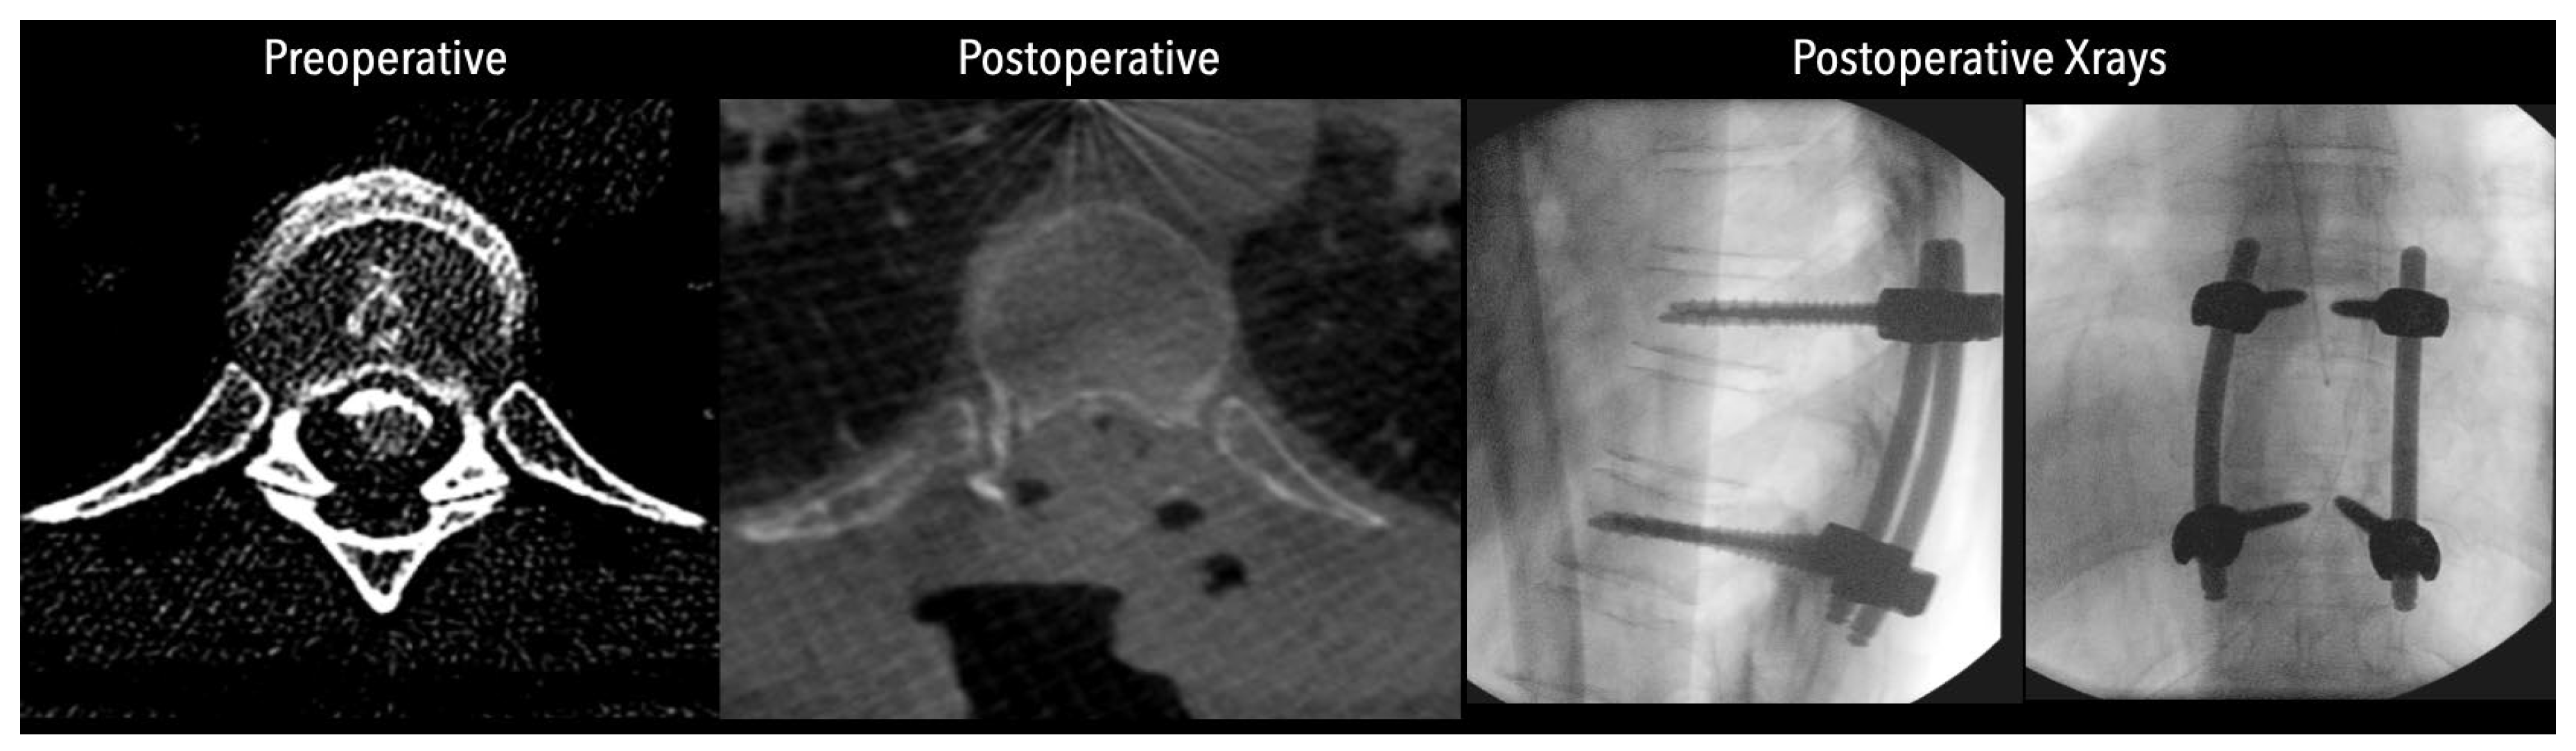

In three of the seven cases, the exiting nerve root at the level of the herniation was ligated due to poor visualization and transected extradurally to improve access. In the remaining four patients, the nerve root was either preserved or dissected intradurally using isocool bipolar diathermy and microsurgical scissors. With gentle medial retraction of the cord under gravity and protection using a micro-patty, the calcified disc was exposed. The ventral dura, when intact, was incised sharply and dissected from the disc surface where possible [Figures 2a,2b,3]. Disc removal was performed using a hockey-stick-shaped Misonix bone scalpel with constant irrigation, guided by intraoperative neuronavigation. The disc material was resected to a depth of 1–2 mm beyond the posterior vertebral wall to ensure adequate decompression. A second O-Arm spin was routinely performed following discectomy to confirm satisfactory decompression, especially given the limitations of the postoperative MRI due to the metal artefact [Figure 4, Figure 5 and Figure 6].

Figure 5. Left side: Comparative pre- and postoperative CT scan of a patient, illustrating complete discectomy. Right side: Postoperative X-rays illustrating fixation.